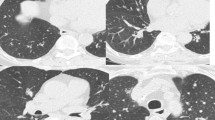

While there are no evidence-based recommendations for the follow-up of healthy individuals with AATD, in general, clinicians treating a large number of such patients do annual or biannual complete pulmonary function testing often accompanied by liver function studies. A baseline high-resolution CT of the chest without contrast can be considered (Fig. 6.1). Interval repetition of the chest CT is not recommended but is reserved for evaluating significant changes in an individual’s respiratory status [26].

Computed tomography of the chest in patients with AAT deficiency shows a broad range of manifestations. AAT deficiency has classically been associated with the development of basilar-predominant panacinar emphysema (Panel a). However, upper-lobe-predominant emphysema (Panel b) and bronchiectasis (Panel c) can also be observed, and sometimes the lungs are normal (Panel d) (reprinted with permission from Ref. [26])